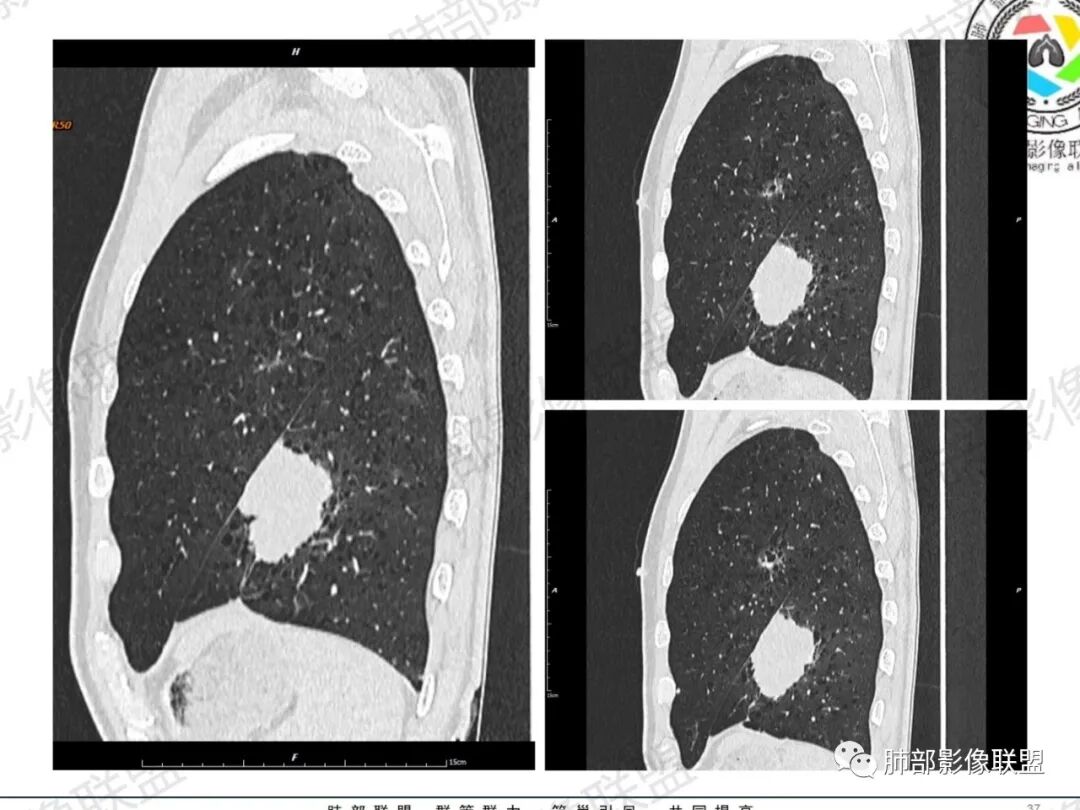

一切∮随缘:左肺下叶不规则肿块,边缘光滑,平直,局部彭隆,分叶,近端支气管堵塞,远端与胸膜相贴,平扫密度尚均匀,增强后不均匀强化,内部可见低密度坏死,胸膜下多发肺气肿,伴双肺散在光滑小结节,实验室肿瘤标志物高,考虑恶性:神经内分泌癌(大细胞),腺癌,鳞癌。

琦遇:恶性没有问题,肺气肿底子、病灶分叶、少许毛刺、叶间胸膜凹陷、部分边缘可见清晰的GGO、胸膜牵拉凹陷、局部胸水、近端支气管截断、部分支气管被推移、占位效应明显、强化特点为不均匀强化、内部有少许沼泽样低强化区,强化部分轻中强化为主、余肺可见转移性结节、左肺上叶似为囊腔型腺癌一枚,肿瘤标志物提示非小、神经内分泌,综合分析考虑大神泌、腺癌、腺鳞癌、鳞癌  同时左肺上叶囊腔型腺癌  肺转移

飞鹰行动:中年人,男性,胸疼入院,左肺下叶占位,张力较高,边界可见分叶,局部可见明显收缩性改变,增强病灶内部有延迟强化表现,考虑恶性病变,大细胞癌伴肺内转移或者囊腔样腺癌伴转移。

蕊:中老年男性,吸烟史,肺气肿背景,左肺上叶类圆形肿块影,边界清晰,边缘凹凸不平,有分叶,支气管进入阻断,临近胸膜栽赃,整体病灶膨隆,局部周围可以清晰ggo,临近叶间裂内凹,轻度强化,并可见多个低密度区,坏死可能,界线不清;肺内多结节,边缘光滑,考虑恶性伴转移,鳞癌、腺癌

傅昌瑜:中老年男性,肺气肿背景,右胸背疼痛1周。CEA、NSE、CYFRA—211升高。左上肺混合磨玻璃结节,内见较多空泡和扩张支气管。左下肺胸膜下肿块,边缘较光滑,深分叶,似有血管进入,与支气管关系不清,内见不均匀强化,见沼泽地样坏死,有胸膜栽赃。另两肺多发圆形小结节。考虑恶性并肺内转移,多原发可能性大,左上肺腺癌,左下肺病理难以判断,小细胞癌?鳞癌?

小锁:中老年男性,肺气肿背景,右胸背疼痛1周。CEA、NSE、CYFRA—211升高。左上肺混合磨玻璃结节,边界清楚,内见较多空泡。左下肺肿块,边缘清楚,深分叶,有血管和支气管进入,胸膜凹陷。另两肺多发圆形小结节。考虑双发原位癌,左上肺腺癌,左下肺大神泌或腺鳞癌可能,肺内转移。

蓝天白云:中年男性,肺气肿背景,左肺下叶肿块,边缘膨隆,有分叶,内有湖泊样坏死,有轻中度强化,局部胸膜栽赃,收缩力不强,周围见肺气肿征象。左肺上叶混合磨玻璃影,边界清楚,考虑都是恶性,左上肺iac,左下肺腺鳞癌,或大细胞肺癌可能。两肺多发结节,考虑转移

毛勤香:老年男性,肺气肿背景,左肺下叶肿块,分叶,边缘光滑,土豆块样,细支气管闭塞,增强轻度不均匀强化,似有坏死,左肺另见多发结节,淋巴结未见明显肿大,恶性确定,吸烟史,鳞癌破坏力强,侵袭力差,多原发的一般很少多于3个,故排后,首先考虑神经内分泌癌,局部血管穿行,鉴别淋巴瘤

周太狼:中年男性,吸烟、高血压史,肿瘤指标升高,肺气肿背景下,左肺下叶肿块影,分叶、膨隆、未跨叶裂,支气管截断,不均匀强化。另双肺多发结节及磨玻璃影,左肺上叶混合磨玻璃,内可见多发空泡影。整体考虑恶性,肺癌伴肺内转移,左下肺鳞癌?神经内分泌癌?左肺上叶囊腔腺癌?